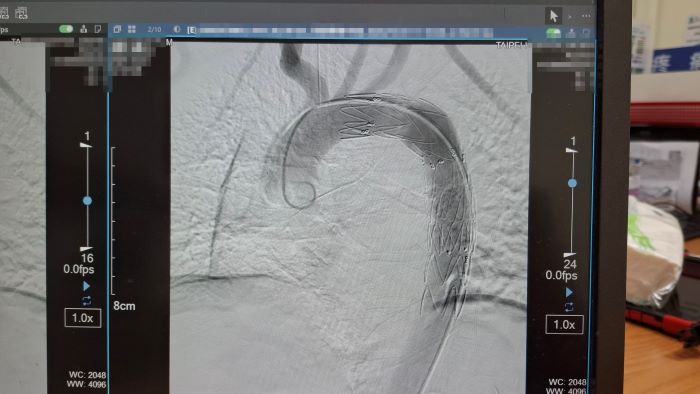

院方緊急會診心臟血管外科醫師孟繁傑,評估後立即施行「胸主動脈腔內血管支架置放手術」,僅在腹股溝處開出不到1公分的小傷口,將支架透過導管送入主動脈破裂處封堵出血點,成功解除致命危機。廖先生術後恢復順利,目前已平安出院。

他說明,「廖先生受傷的位置位於主動脈弓與降主動脈交界處的峽部(isthmus)。」,這裡是胸部外傷最常見的主動脈破裂位置,因為主動脈在此處轉彎固定,當胸部受到強烈撞擊時,產生的剪力容易造成血管撕裂,形成假性動脈瘤。如果沒有及時發現,一旦包覆性破裂轉為完全破裂並引發大出血,存活機率幾乎為零。

過去治療此類重症,多須進行傳統側身開胸手術,手術傷口可長達30至40公分,且術中需使用高劑量抗凝血劑。對於同時合併多重外傷的患者而言,容易導致其他部位出血,手術風險相當高。

孟繁傑表示,近年來,主動脈腔內血管支架置放手術逐漸成為主流治療方式。醫師只需從腹股溝股動脈置入導管,將金屬支架精準送到破裂位置撐開血管並封住破口,不僅傷口小、手術時間短,也能降低出血與併發症風險。目前此項治療方式已被美國血管外科學會列為主要治療建議,台灣健保也已納入給付,讓患者能以較低負擔接受先進治療。